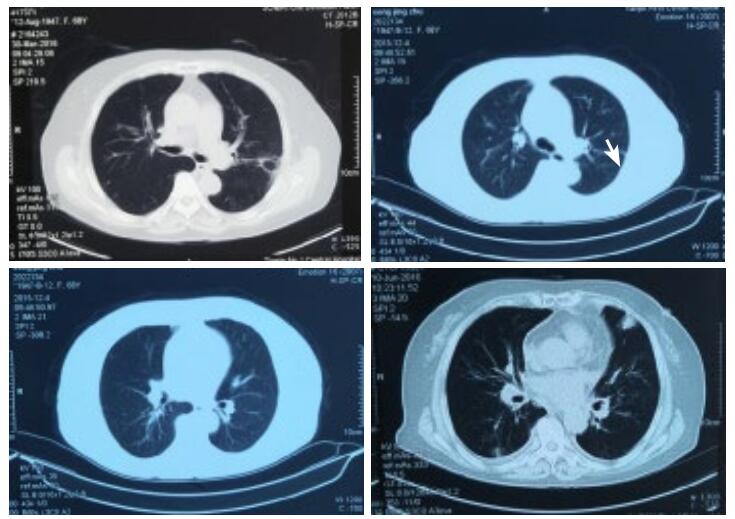

第1天,心脏超声提示:左房38 mm,左室舒张末内径50 mm,射血分数50%。左室下壁后壁运动减低,左室收缩功能减低,心律失常,二、三尖瓣轻度反流。血化验回报:血常规:白细胞(WBC)15.32×109/L,中性粒细胞(NEUT)比例55.64%,嗜酸性粒细胞(Eosinophil,EO)比例18.81%(绝对值2.88×109/L)。入院后给予左西孟旦等药物对症治疗。第3天,血常规回报:WBC 13.07×109/L,NEUT比例44.0%,EO比例42.0%(绝对值5.49×109/L)。第4天,复查血常规回报:WBC 12.6×109/L,NEUT比例43.6%,EO比例36.9%(绝对值4.6×109/L),复查cTnT 4.16 ng/mL;NT-proBNP 13 840 pg/mL。患者症状略缓解。追问病史:入院前1年曾3次就诊于外院,且反复多次出现EO异常升高,最高2.32×109/L,动态对比胸部CT情况可见游走性斑片影,且入院前1周行冠脉CTA检查未见异常。故考虑Löffler心内膜炎可能。第5天,给予甲强龙40 mg静脉,第6天复查血常规WBC 7.2×109/L,NEUT比例87.2%,EO比例0.5%(绝对值0.0×109/L)。持续给予甲强龙40 mg静脉5 d,第10天复查血常规WBC 9.5×109/L,NEUT比例70.1%,EO比例0.7%(绝对值0.1×109/L);cTnT 2.24 ng/mL;NT-proBNP 6 481 pg/mL,住院期间查ANCA阴性,曲真菌抗体阴性、C反应蛋白、降钙素原、体液免疫、风湿全项均正常。入院后11 d症状好转出院。

| 图 2 入院前1年多次胸部CT情况(箭头所示游走性斑片影) |

患者因心前区不适入院。急诊查cTnT及NT-proBNP明显异常,提示心肌损伤、心功能不全诊断明确。但入院后反复复查血常规,EO均明显升高,且患者入院前1周行冠脉CTA未见异常,加之入院后心肌酶、心电图不符合AMI动态演变过程。另外患者1年内多次入院均出现EO均异常升高(均大于 > 1.5×109/L),提示存在嗜酸性粒细胞增多症,胸部CT可见游走性斑片影,提示存在嗜酸性粒细胞增多综合征[1]。尽管未做心肌活检,但患者具有心血管系统、呼吸系统损害,EO计数反复大于 > 1.5×109/L,故笔者认为Löffler心内膜炎诊断明确。